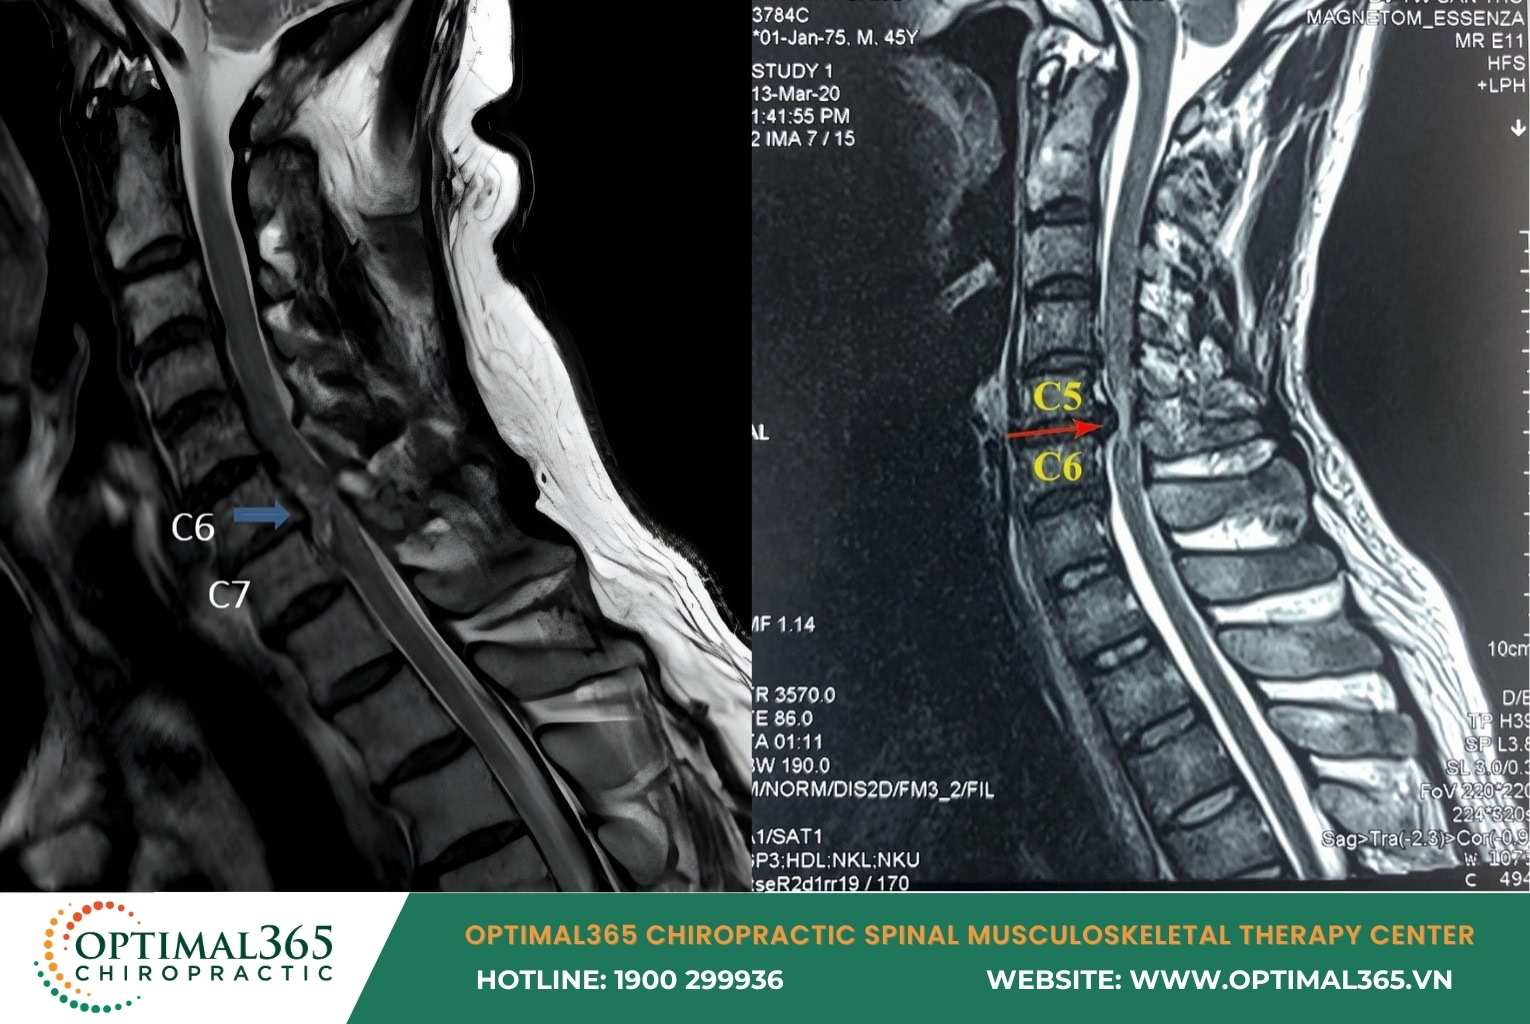

In subclinical cases, cervical herniated disc symptoms are detected via MRI showing: Disc herniating anteriorly or posteriorly, nucleus pulposus displaced, spinal structure changes, and compression on nerve roots or spinal cord.

A diagnostic imaging case of cervical disc herniation at the C6–C7 and C5–C6 levels